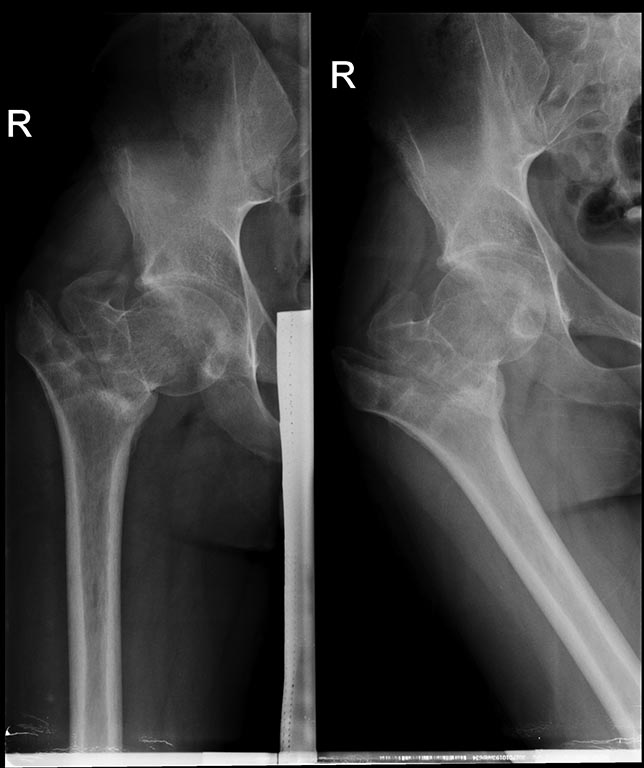

Не вижу никаких признаков артроза. Клиника спустя 4-5 месяцев после перелома очевидна и тривиальна.

Головка правильной формы. 23 года. Варусная деформация проксимального отдела бедра. Никаких других существенных факторов не упомянуто. Исходя из представленной информации - кроме коррекции варусной деформации тем или другим способом, нет других направлений поиска решения. Ампутация здорового тазобедренного сустава в 23 года - идиотизм, извините за прямоту.

При внесуставной посттравматической варусной деформации нас мало интересует структура головки - просто потому, что в такой ситуации ничего с ней страшного не бывает, кроме дефектов от предшествующих имплантатов. Важна только форма головки, сохранность суставной поверхности. Если головка сферична - в любом возрасте, и уж тем более в молодом, операция выбора - это устранение варусной деформации.